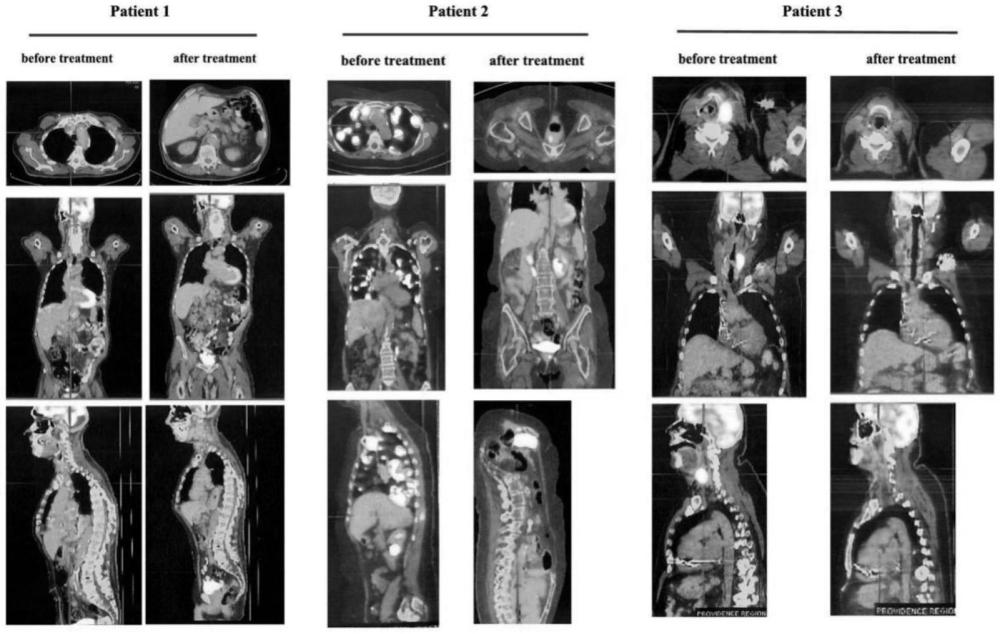

| 摘要: | 本发明提供了苯达莫司汀联合利妥昔单抗在制备调节机体免疫能力药物中的应用,特别是在制备治疗DLBCL合并心功能不全症状的抗肿瘤药物中的应用。 | ||||